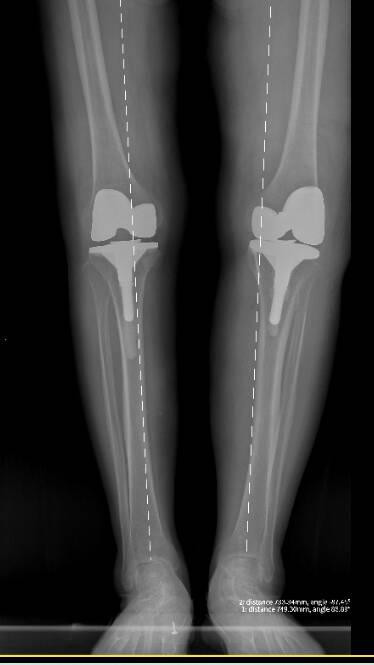

全长术后

2025年6月,首先为畸形和疼痛更重的右膝实施关节置换,术后恢复良好;

2025年7月,再次顺利完成左膝置换手术。